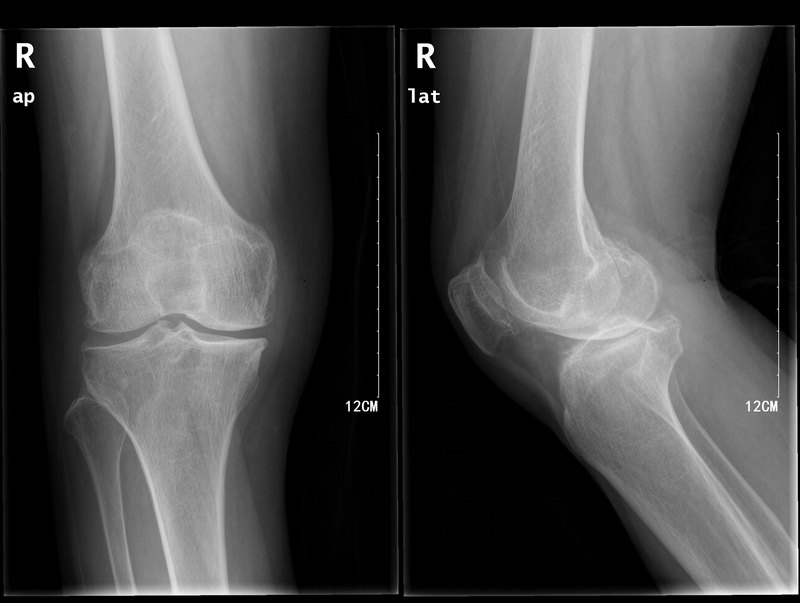

人類自從直立行走,解放了雙手,可以做更多的事情,但同時因為僅靠雙下肢負(fù)重行走,隨著年齡的增加,大部分人都會出現(xiàn)不同程度的膝關(guān)節(jié)退行性變,簡單的說就是膝關(guān)節(jié)老化、磨損。(醫(yī)學(xué)名詞叫膝關(guān)節(jié)骨性關(guān)節(jié)炎)。而這種老化、退變是不可逆的。所以當(dāng)老年患者出現(xiàn)膝關(guān)節(jié)行走疼痛,下蹲困難,嚴(yán)重影響生活。而晚期的骨性關(guān)節(jié)炎往往需要做關(guān)節(jié)置換術(shù)才能緩解疼痛,改善功能。 那么是不是一旦發(fā)生膝關(guān)節(jié)炎就只能等到關(guān)節(jié)變形、走路困難才能手術(shù)處理呢? 就好比一顆牙壞了,一定要等到它不能用了才拔掉裝假牙呢?當(dāng)然不是,可以補牙!而膝關(guān)節(jié)單髁置換術(shù)就好比是補牙一樣!而補好的牙往往和自己的牙一樣好用,往往可以用很久,甚至終生。 單髁置換術(shù)也是一樣,術(shù)后的效果非常理想,患者的功能都非常好,幾乎感覺不到做過手術(shù),而且很大一部分患者也可以終生不需要再做全膝關(guān)節(jié)置換術(shù)。 所以,單髁置換術(shù)被稱作保膝手術(shù)!(保住了膝關(guān)節(jié))。 單髁置換術(shù)后當(dāng)天就可以下地行走,一周左右就可以出院。一個月左右可以恢復(fù)日常活動。手術(shù)出血少,傷口小,恢復(fù)快。目前全世界都在運用這項技術(shù),造福膝關(guān)節(jié)炎患者,讓他們遠(yuǎn)離疼痛,保持健康,更好的享受人生。

很多骨關(guān)節(jié)疾病,如股骨頭壞死, 骨性關(guān)節(jié)炎,類風(fēng)濕性關(guān)節(jié)炎,強(qiáng)直性脊柱炎,髖關(guān)節(jié)發(fā)育不良,到了晚期,走路時關(guān)節(jié)面就會變成骨對骨的磨損,出現(xiàn)明顯的疼痛,變形,日常生活極為不便,生活質(zhì)量大大降低。這個時候人工關(guān)節(jié)置換術(shù)就能解決關(guān)節(jié)疼痛畸形活動不便的問題。 雖然髖膝關(guān)節(jié)置換手術(shù)是20世紀(jì)發(fā)明的最成功的手術(shù)之一, 但是一談到關(guān)節(jié)置換都會談虎色變,認(rèn)為要換掉整個關(guān)節(jié),是一種很大很恐怖的手術(shù),其實這是一個誤解,關(guān)節(jié)置換手術(shù),要置換的都是關(guān)節(jié)面,而不是整個關(guān)節(jié),如膝關(guān)節(jié)的置換其實就是換掉磨損壞的部位,是一種表面置換,不是整個關(guān)節(jié)都換掉,根據(jù)表面置換的面積不同分為部分置換暨單髁置換和全表面置換?,F(xiàn)在通過我們技術(shù)的改進(jìn)和努力,病人術(shù)后1天就能下地走動,術(shù)后三五天就可以出院回家,已經(jīng)變成了一個沒有疼痛很少輸血快速康復(fù)的普通手術(shù)。 手術(shù)以后效果到底怎么樣呢?大家看看病友術(shù)后贈給我的錦旗就明白啦。